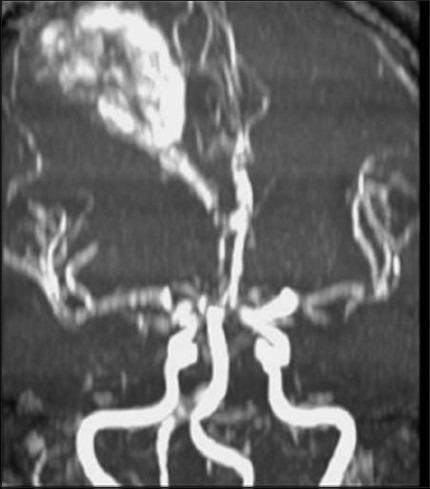

We describe an atypical case of a patient with no risk factors who developed sudden eclampsia and spontaneous intracerebral hemorrhage during the 34(th) week of pregnancy. She underwent successful emergent Cesarean section followed by craniotomy. Both intraoperative surveillance and postoperative magnetic resonance angiographic examination of the cerebral vessels failed to identify an aneurysm, arteriovenous malformation, tumor, or leptomeningeal disease.

我们描述了一例非典型病例,该患者无危险因素,在妊娠第34周时突然发生子痫和自发性脑出血。她成功接受了急诊剖宫产,随后进行了开颅手术。术中对脑血管的监测以及术后的磁共振血管造影检查均未发现动脉瘤、动静脉畸形、肿瘤或软脑膜疾病。